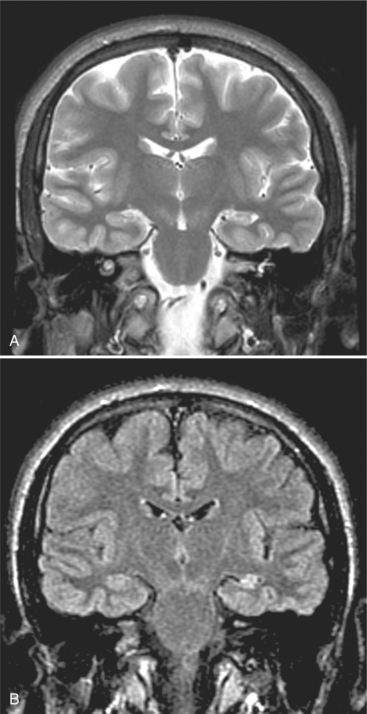

About 70% to 80% of complex partial seizures arise from the temporal lobe, and more than 65% of these originate in mesial temporal lobe structures, especially the hippocampus, amygdala, and parahippocampal gyrus. Remaining cases of complex partial seizures arise mainly from the frontal lobe, with smaller percentages originating in the parietal and occipital lobes. Hippocampal or mesial temporal sclerosis, or scarring, is characterized by variable degrees of pyramidal cell loss and gliosis in the hippocampal subfields and dentate gyrus. This condition represents the most common pathologic substrate of partial epilepsy in adolescents and adults.11 Fig. 36-1 shows mesial sclerosis identified through coronal magnetic resonance imaging (MRI).

Figure 36-1 Temporal mesial sclerosis—coronal magnetic resonance image (MRI). The coronal projection is essential to reveal hippocampal abnormalities. Fluid-attenuated inversion recovery (FLAIR) MRI is superior to T2 weighting to show signal abnormalities, because the saturation nullifies the signal from the cerebrospinal fluid. A, A T2-weighted scan shows volume reduction of the left hippocampus. B, A FLAIR sequence shows the abnormal high signal (arrow), not seen on the T2 scan. (From Adam A, Dixon AK, Grainger RG, et al, eds: Grainger and Allison’s diagnostic radiology: a textbook of medical imaging, ed 4, Philadelphia, 2001, Churchill Livingstone.)